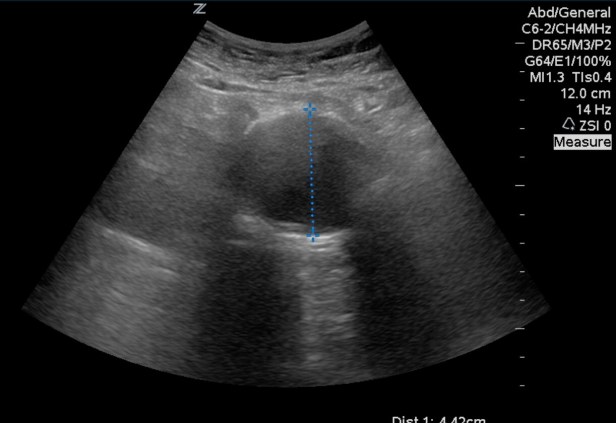

When measuring the abdominal aorta you need anterior to posterior OUTER diameter. Not inner diameter. This was large enough it didn’t matter.